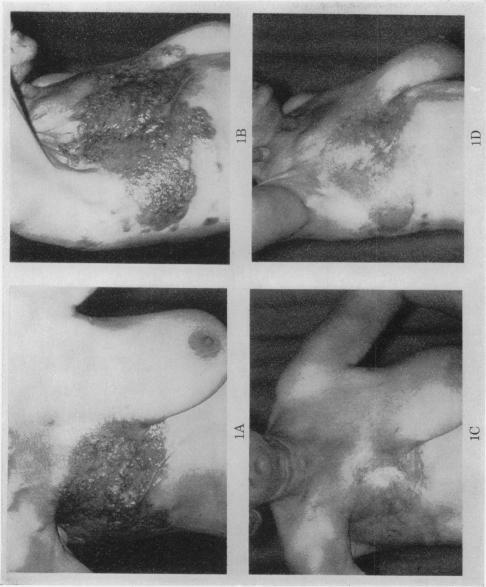

Seventy-five cases of malignant solid tumours treated by a quadruple chemotherapy regime are described. These tumours originated in the breast, head and neck, bronchus, genital tract, cutaneous melanoma, soft tissue and gastro-intestinal tract. All 14 patients with breast carcinoma underwent remission and in 6 this was complete. Significant remissions were seen in gastro-intestinal and head and neck malignancies, and also in the soft tissue group. A short response was noted in 6 of 14 cases of bronchial carcinoma. Malignant melanoma, testicular, ovarian and cervical carcinomata failed to respond.In all, 40 of 75 patients underwent objective remission.